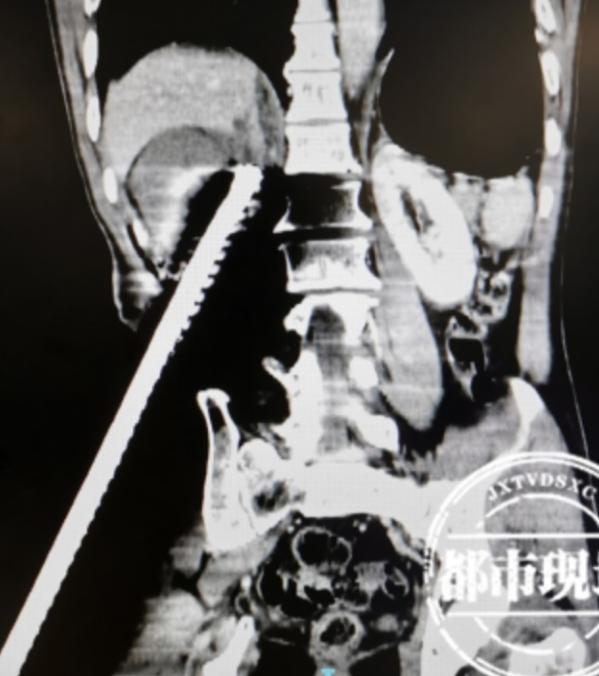

5月10日,57歲的劉師傅在南昌市內(nèi)一個工地上干活的時候,一不留神從高處跌落,兩根鋼筋插入了腹部。

醫(yī)生介紹,劉師傅被送到醫(yī)院時,雙側都插了一根鋼筋,左邊傷勢在工地附近的醫(yī)院進行了處理,沒那么嚴重,而右邊的穿透很深,大概15公分。從CT看,鋼筋穿透了腎臟,可能造成下腔靜脈和腎靜脈損傷。

情況緊急,醫(yī)院啟動多學科聯(lián)合會診,通過手術,鋼筋被拔出。

南昌大學一附院泌尿外科副主任郭炬:把這個腎臟慢慢地小心翼翼地游離出來,手術中看到下腔明顯有很大破口,腎靜脈也有個破口小心跟他縫起來,之后拔出鋼筋。腎臟有貫通傷,保留下來沒有任何價值,所以對腎臟進行了切除。